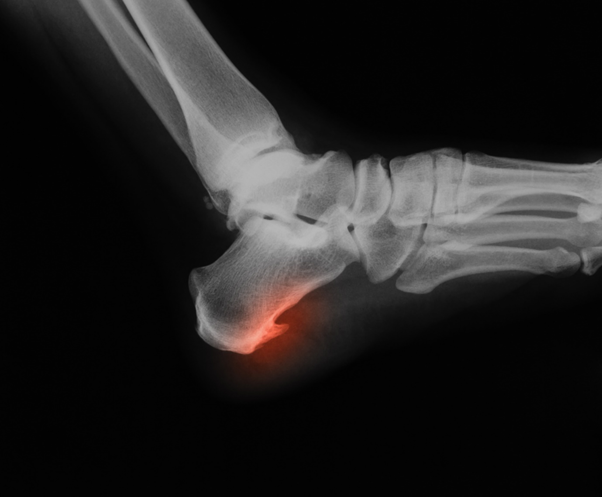

Пяточная шпора представляет собой костный нарост из пяточной бугристости (пяточной кости). Пяточные шпоры обычно обнаруживаются при рентгеновском исследовании. Это форма экзостоза.

Пяточная шпора может быть как самостоятельным образованием, так и следующей стадией развития подошвенного фасциита. Но, и в том и в другом случае причиной формирования шпоры становится повреждение связки в результате перегрузки области соединения фасции с пяточной костью. При повреждении подошвенной фасции в месте ее прикрепления к пяточной кости организм начинает укреплять соединение связки с костью, в результате чего и формируется костный нарост - остеофит. Кроме образования шипа или шпоры на пятке в месте повреждения фасции происходит воспалительный процесс. Именно он создает боль в момент опоры на стопу. При пяточной шпоре боль больше смещена к центру пяточной кости или к задней её части.